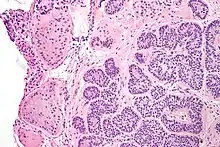

Micrograph of a Sertoli cell nodule. H&E stain.

A Sertoli cell nodule is a benign proliferation of Sertoli cells that arises in association with cryptorchidism (undescended testis).[1] They are not composed of a clonal cell population, i.e. neoplastic; thus, technically, they should not be called an adenoma.[2]

Sertoli cell nodules are unencapsulated nodules that consist of:[2][3][4]

- cells arranged in well-formed tubules (that vaguely resemble immature Sertoli cells), with

- bland hyperchromatic oval/round nuclei that are stratified, and

- may contain eosinophilic (hyaline) blob in lumen (centre).